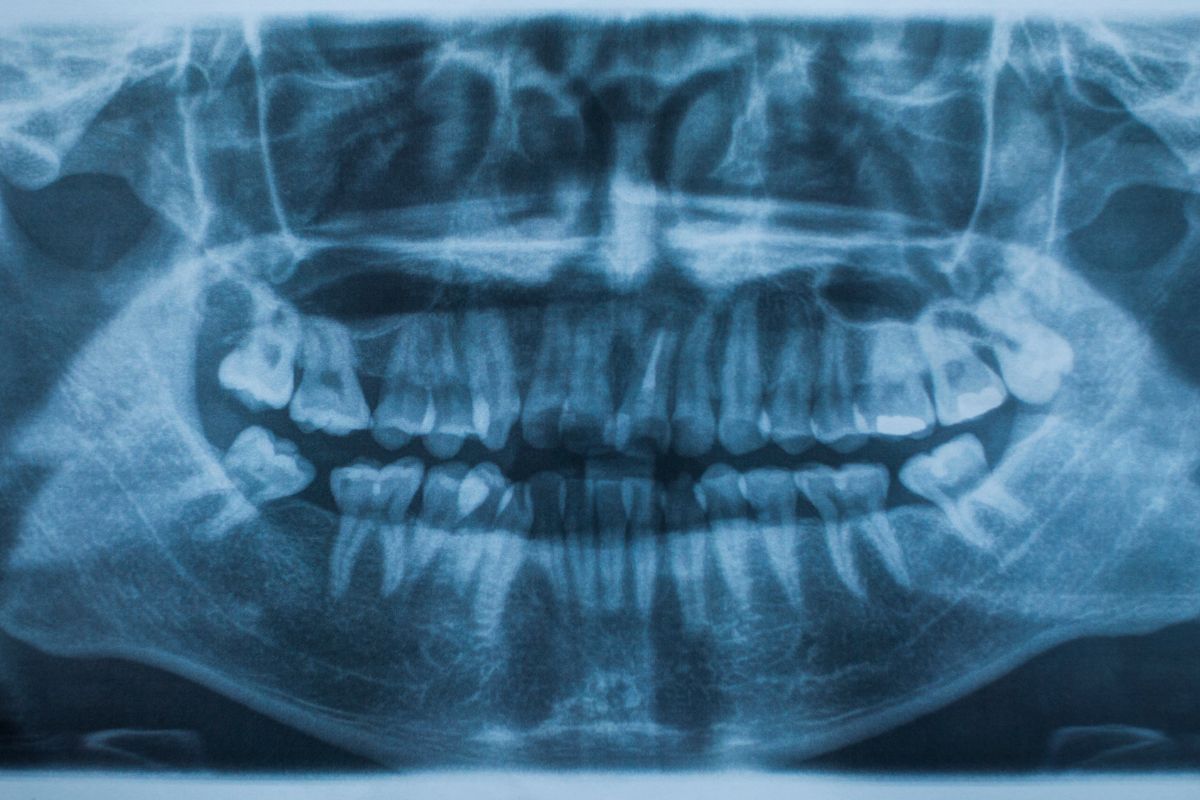

Un traumatismo dental se refiere a cualquier daño causado a los dientes y tejidos circundantes debido a un golpe o impacto. Las manifestaciones pueden variar desde una fractura mínima hasta la pérdida completa de un diente. Es esencial acudir al dentista cuanto antes para evaluar el daño y recibir el tratamiento adecuado.

Al enfrentar un traumatismo dental, es esencial no dejar pasar mucho tiempo antes de visitar al dentista. Un diagnóstico temprano puede prevenir futuros problemas y asegurar que los dientes afectados recobren su funcionalidad y estética. Además, abordajes como la endodoncia pueden ser necesarios para tratar el daño interno invisible a simple vista.